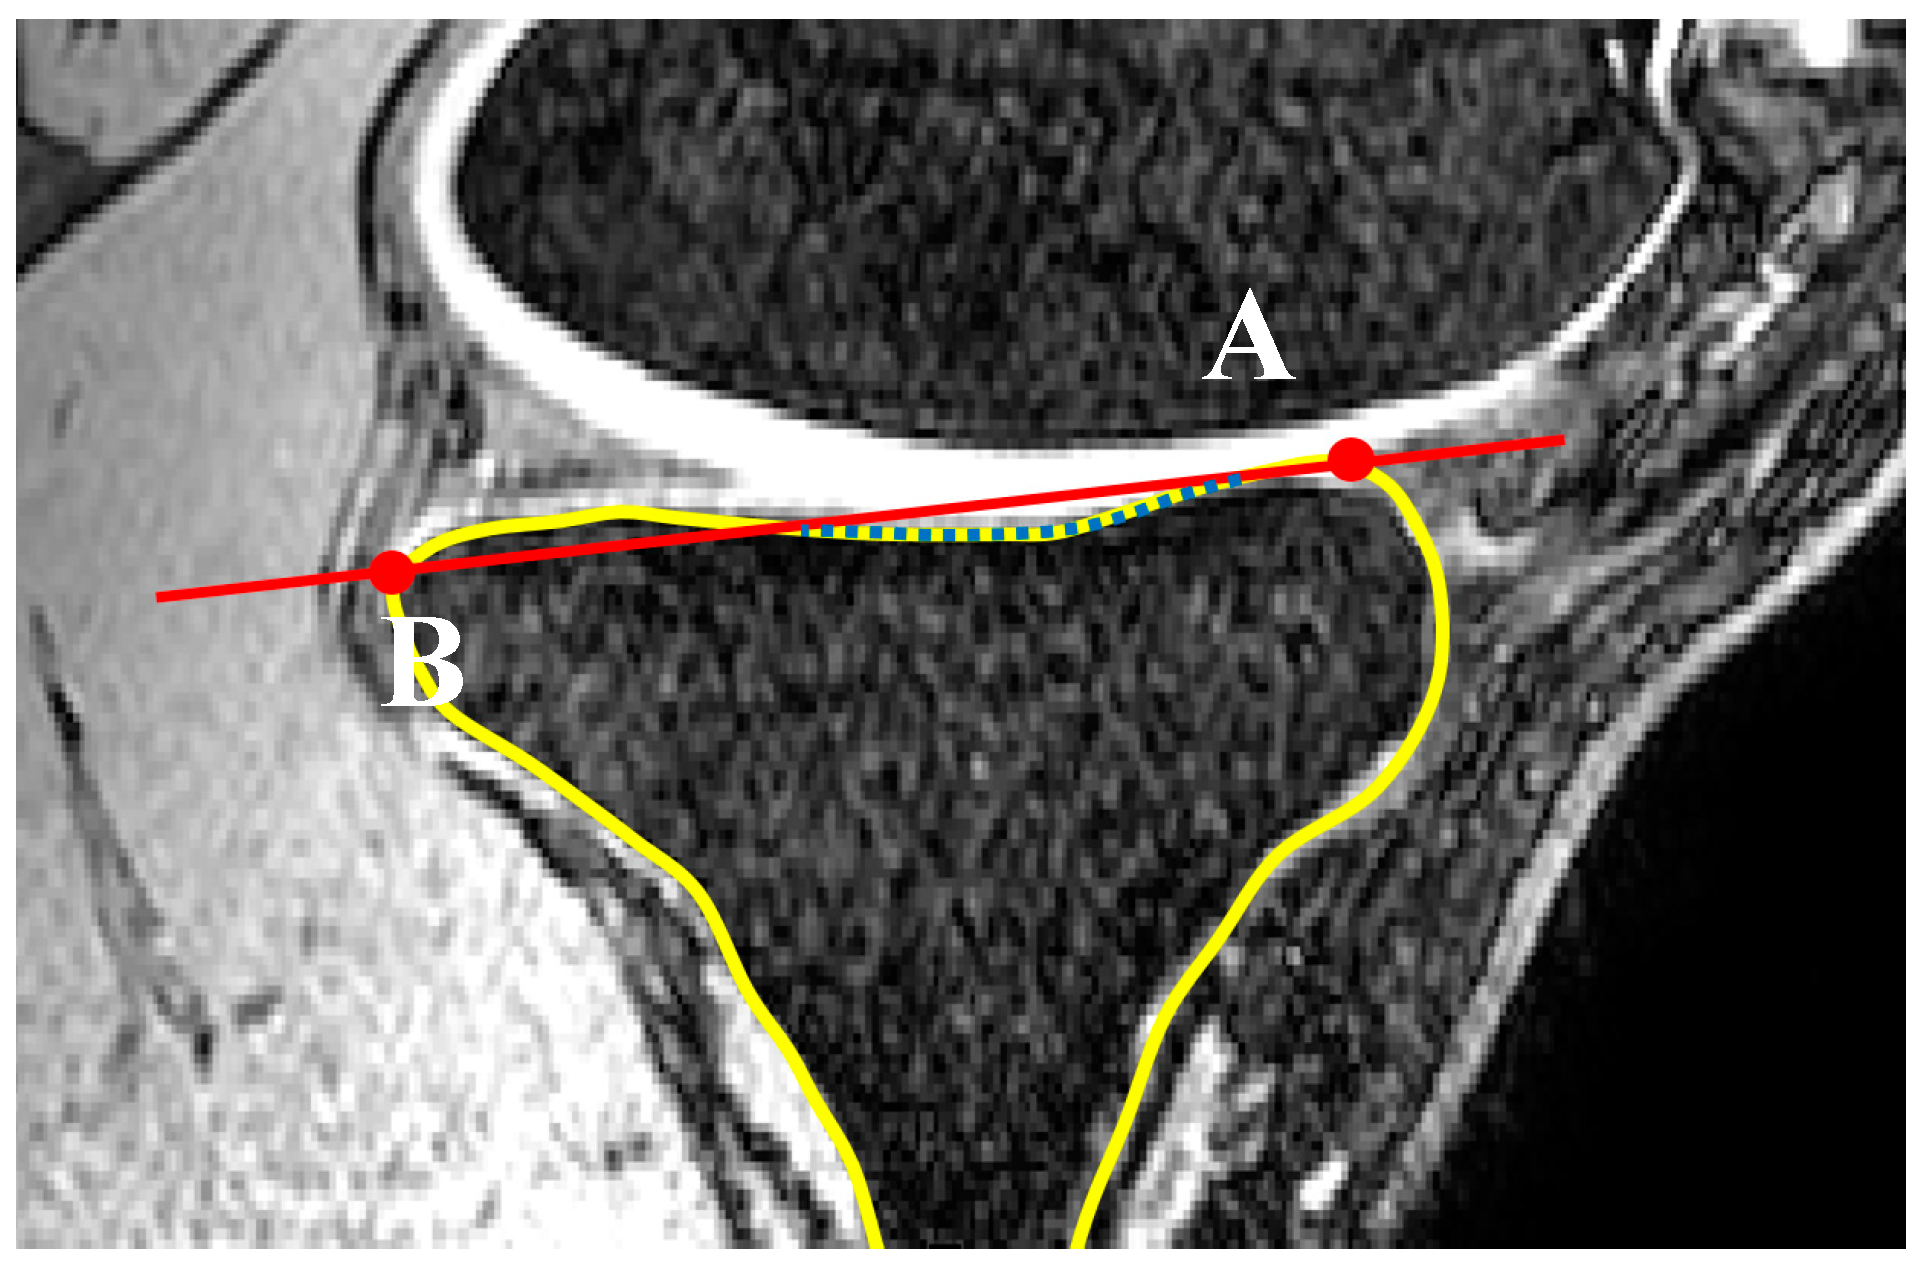

2.1. Medial and Lateral Tibial Slope Measurement Methodology

2.3. Concavity Zone